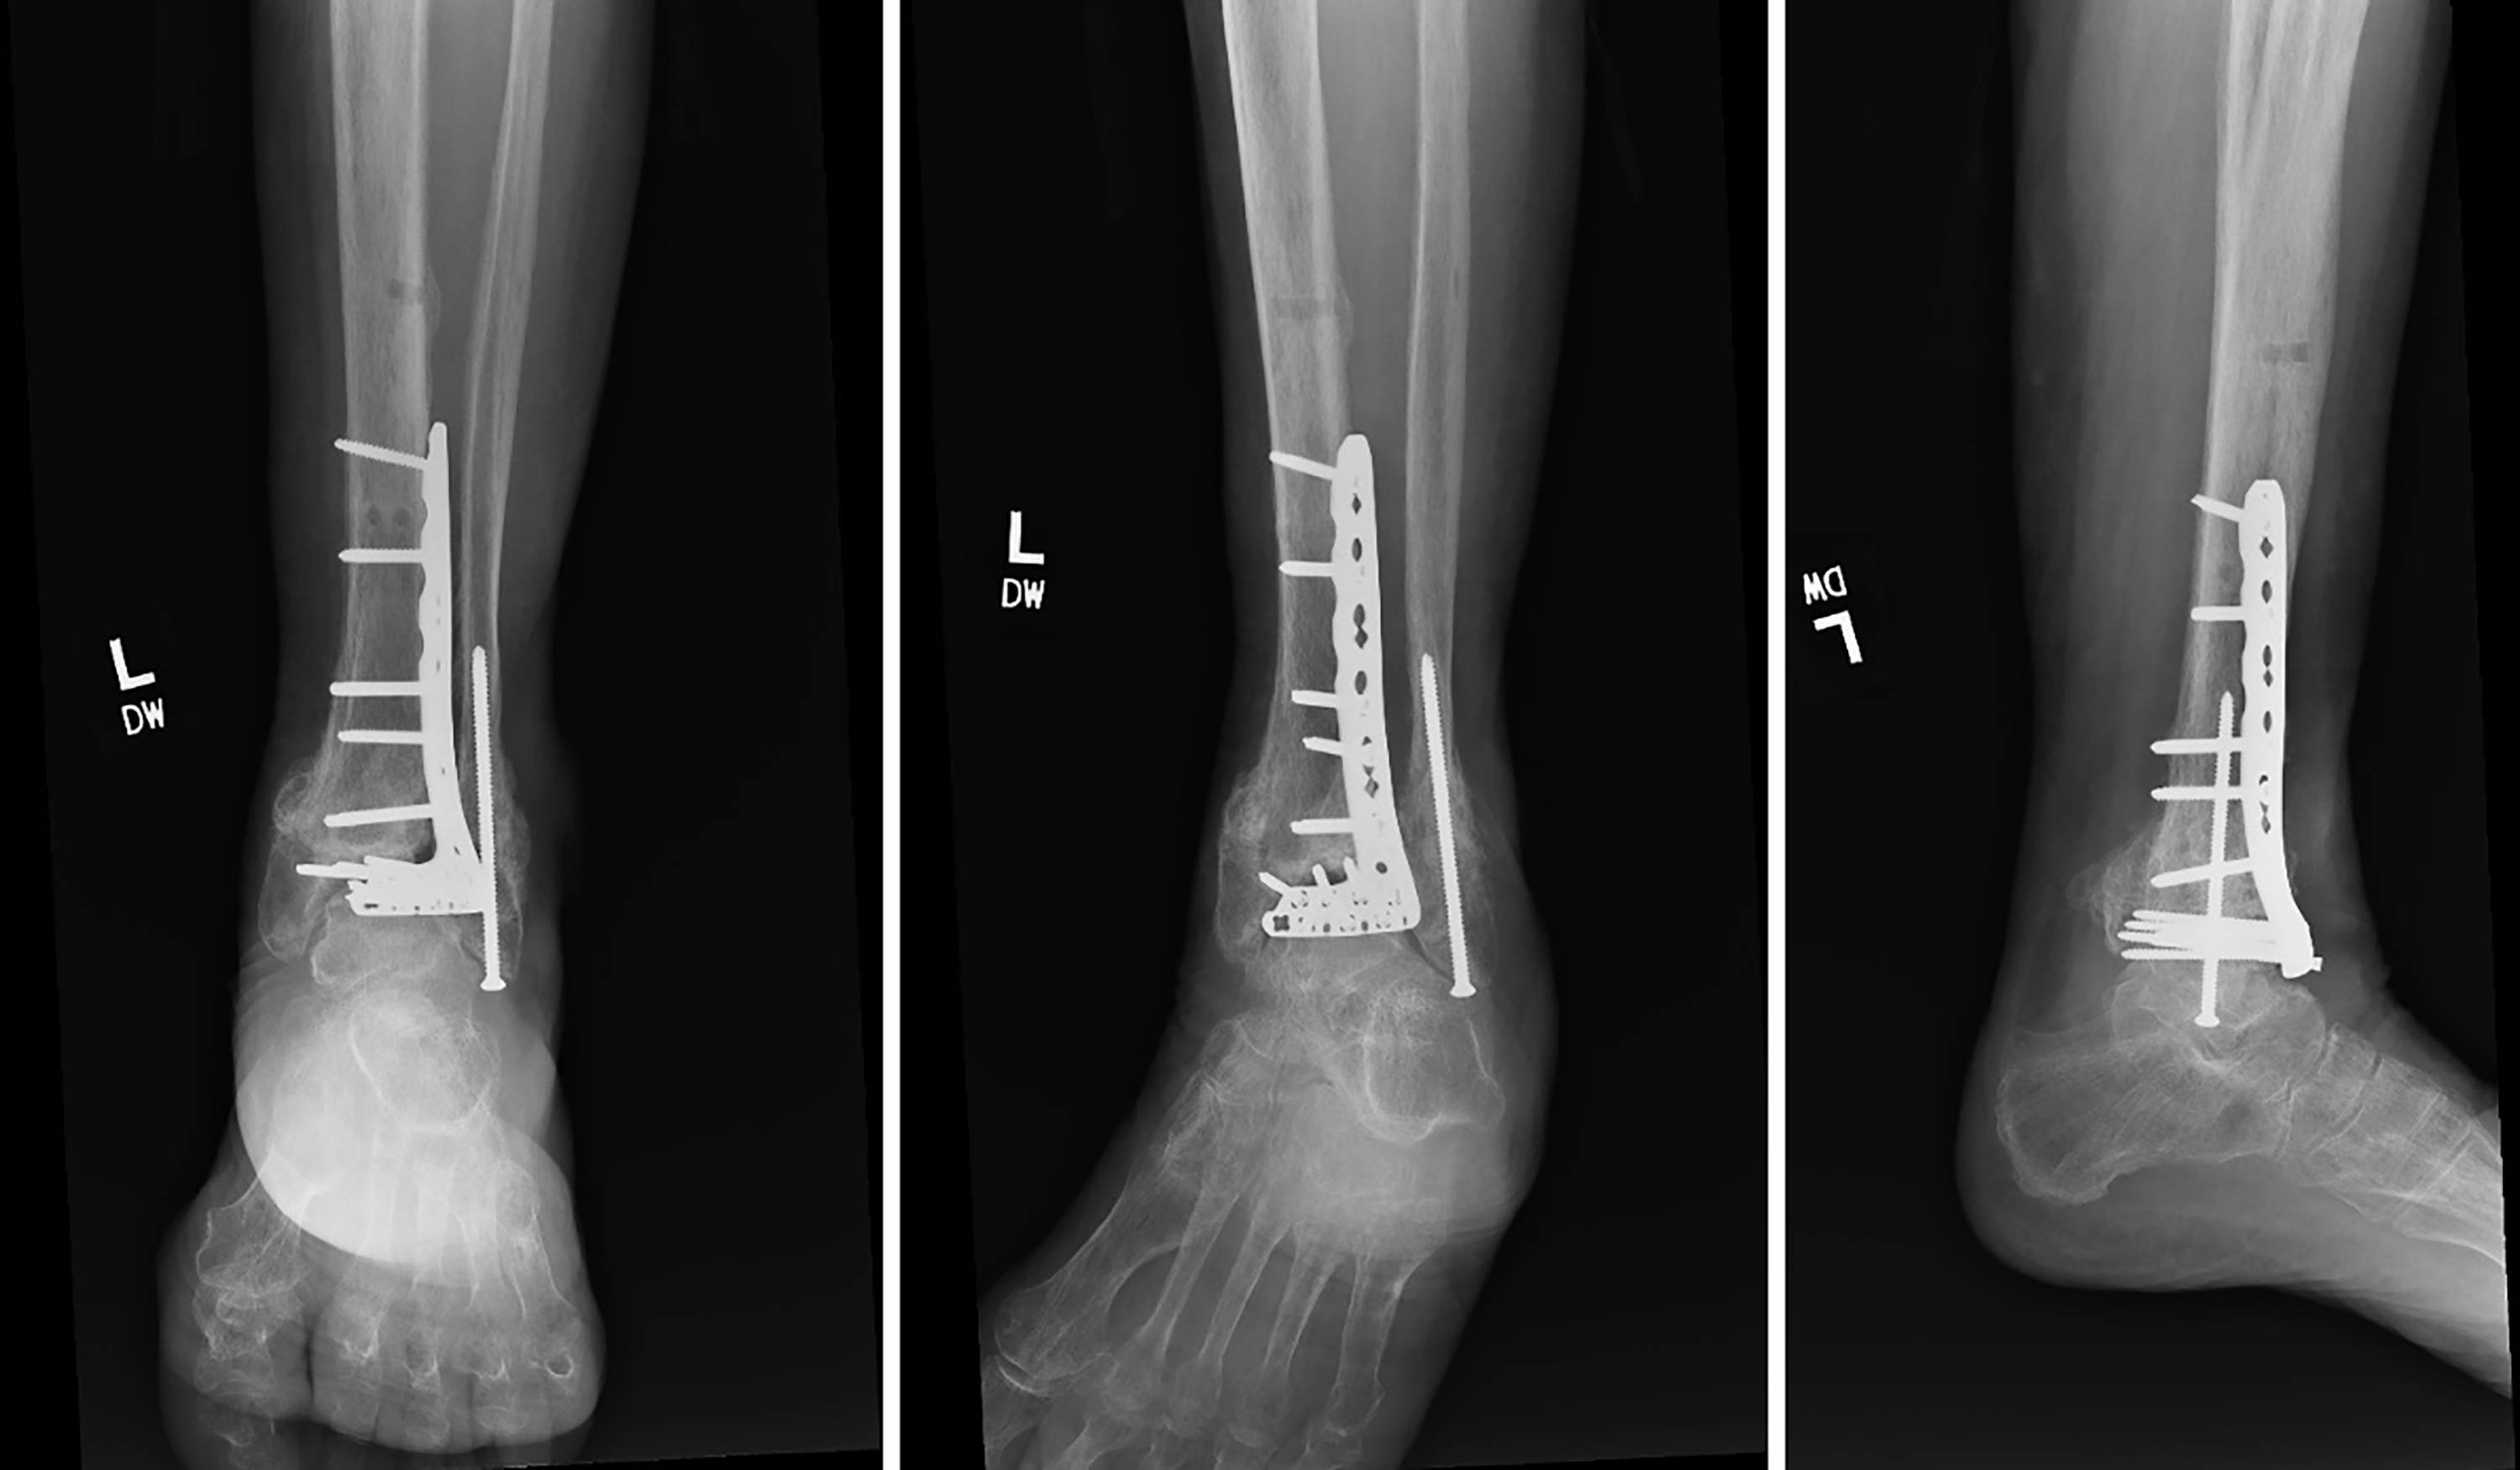

Intraoperatively, the sinus tract to the anterolateral ankle was excised in a 3:1 elliptical fashion and all nonviable tissue was removed. The ankle joint was then exposed through the prior incision. There was extensive liquefactive necrosis and an apparent biofilm coating over the hardware, which was debrided in its entirety. Complete osteolysis of the distal tibial epiphysis was evident, such that there was wear artifact on the talus indicative of intra-articular screw migration. Following debridement and hardware removal, an antibiotic spacer was fashioned with PMMA including 1 g of vancomycin and 1.2 g of tobramycin. Prior to insertion, fabrication of a small anterior fin extending from the lateral caudal portion of the spacer was constructed. This anterior fin was placed interpositionally in the tibiofibular syndesmosis to the level of the incisura once the cement started to harden. This was performed to increase stability and potentially improve its longevity (Fig. 4).

Figure 4. Postoperative radiographs exhibiting a PMMA-AEC spacer fabricated with an anterior syndesmotic “fin” stabilized in the tibiofibular syndesmosis.